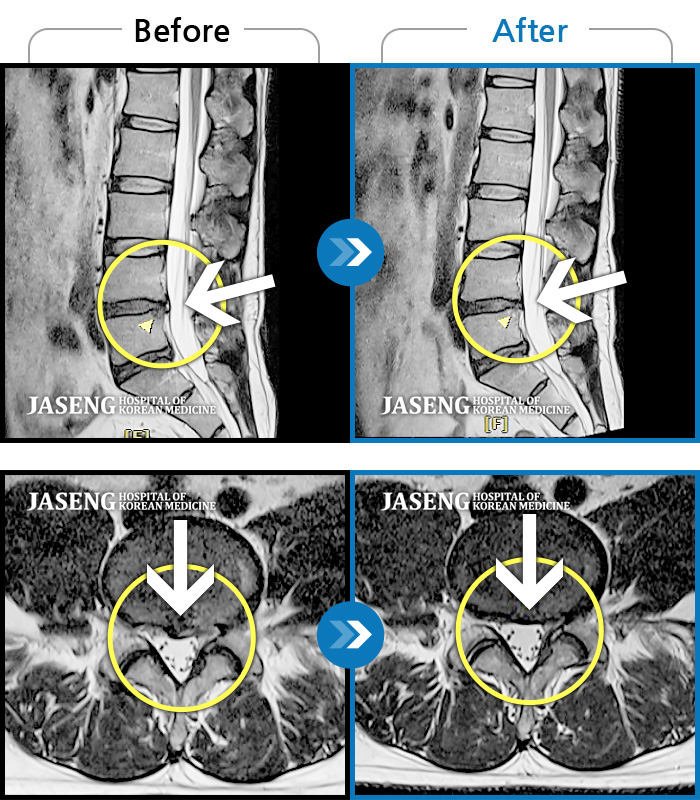

MRI 치료사례

허리디스크

광주 · 장영우 원장

양측 허리부터 골반 묵직한 통증, 좌측 다리 외측까지 이어지는 당기는 통증으로 내원하셨습니다.

촬영시기

2503.04.01 ~ 2509.11.01